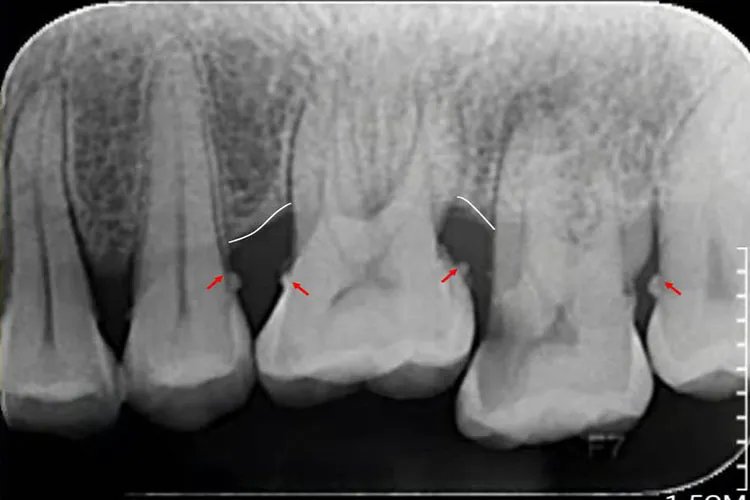

龈下牙结石多在龈缘以下,肉眼看不到,在X线片上可见。呈褐色或黑色,较龈上牙结石体积小而硬,一般与牙面的附着比龈上牙结石更牢固。